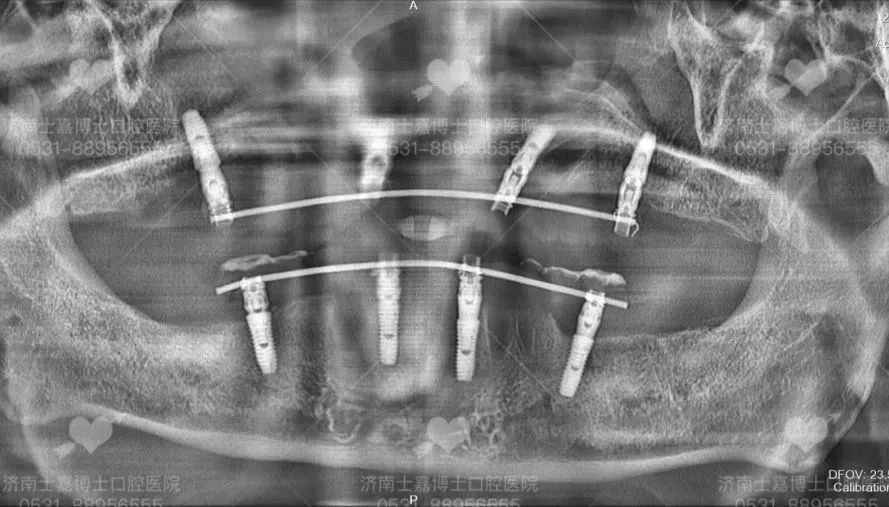

舒适化牙齿种植后 老人种植后牙齿状况 口腔X光片 术后的老先生很快恢复了意识,仍处在观察期的他已经迫不及待吃上肉包子,由衷的感叹:太好了~